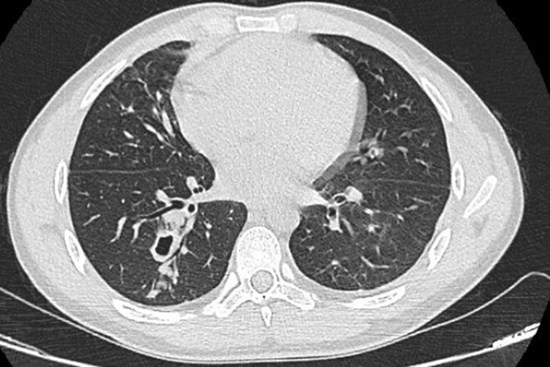

Nam thanh niên bị tràn khí màng phổi nhưng khi hút dịch phổi, bác sĩ phát hiện bên trong có nhiều sinh vật ngoe nguẩy.

Sán lá phổi hoành hành trong phổi của nam thanh niên, khi được tra hỏi mới vỡ lẽ là do thói quen ăn sống món ăn quen thuộc này.

Thói quen ăn gỏi hải sản hoặc ăn tôm, cua cá chưa được nấu chín có nguy cơ cao bị nhiễm sán lá phổi. Gây ra những bệnh lý về phổi, tổn thương phổi do ký sinh trùng.